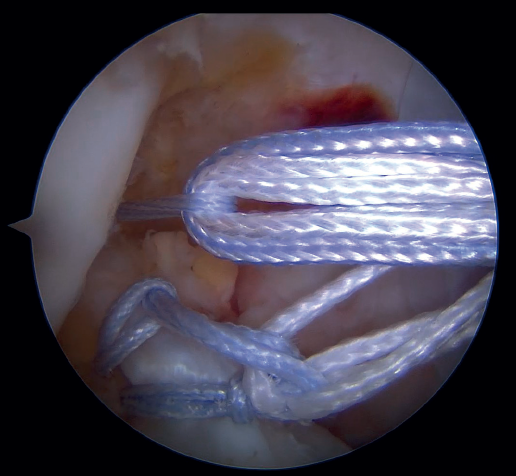

Then, and also through the cannula, arthroscopic suture forceps (KneeScorpion®, FirstPass® Mini) loaded with an ultra-high strength suture specific for this technique (FiberRing®) is introduced. Using the forceps, the suture thread is passed through the distal third of the stump of the ACL, with both ends exiting through the cannula after removal of the instrument from the joint. After removing this first thread, the steps are repeated in identical fashion with a second suture, which now passes through the ligament in a more proximal position. It is very important that these two sutures pass completely through the full thickness of the ACL.

Our attention now turns to outside the knee, where the loop of the cortical suspension system (ACL Repair TightRope®) is secured to the ACL using the FiberRing® sutures. This device is a cortical suspension button with a loop of variable length, which also incorporates a high strength tape. To secure it, the suture marked as "1" on the card is first passed through the retriever thread of one of the FiberRing® sutures, and then the step is repeated through the retriever thread of the remaining FiberRing® suture. Next, this thread passing through the rings of the FiberRing® system is passed through the closed loop marked as "2". Finally, this thread is passed through the nitinol marked "3"; the card is held firmly and the nitinol is pulled so that the TightRope® thread passes through the cortical plate. At this point, part of the loop, the button and the threads connected to it (loop traction sutures, button lift sutures and high strength tape) remain outside the knee, waiting to be inserted into the joint (Figure 8).

The next step is to remove the femoral retriever thread through the cannula of the anteromedial portal, loading it with the traction and flipping sutures, but not with the high strength tape. By pulling on the retriever thread, the ACL RepairTightRope® sutures will pass through the femoral tunnel (Figure 9), exiting through the skin. Using the lift sutures, the button is then likewise advanced through the tunnel until it is flipped over the lateral femoral cortex (which can be checked by pulling firmly on the high strength tape, which still exits through the cannula). At this point, all that remains is to pull alternately on both loop traction sutures to shorten the loop and reduce the stump of the ACL until contact is made with its native footprint.